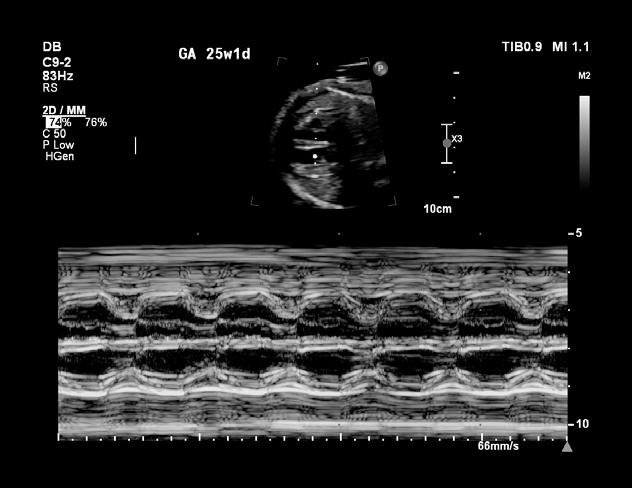

La tétralogie de Fallot est la plus fréquente des cardiopathies congénitales cyanogènes, représentant près de 8 % d’entre elles. Cette malformation tire son nom d’Étienne-Louis Arthur Fallot, qui l’a décrite en 1888.

La tétralogie de Fallot se caractérise par quatre anomalies distinctes, comme ÉtienneLouis Fallot, anatomopathologiste, les avait observées lors d’autopsies. En réalité, deux de ces anomalies suffisent à expliquer la physiopathologie de cette malformation, les deux autres n’étant que des conséquences. Cette introduction vise à offrir un aperçu des caractéristiques cliniques, des défis diagnostiques et des approches thérapeutiques actuelles de cette pathologie (figure 1 ).

Signes et symptômes

Nouveau-né et nourrisson

À la naissance, le nouveau-né est souvent bien coloré, rose, et ne présente pas de gêne particulière. Cependant, la présence d’un souffle cardiaque systolique, perçu dès l’auscultation en salle d’accouchement, attire l’attention. Un souffle d’apparition précoce nécessite une échocardiographie d’urgence.